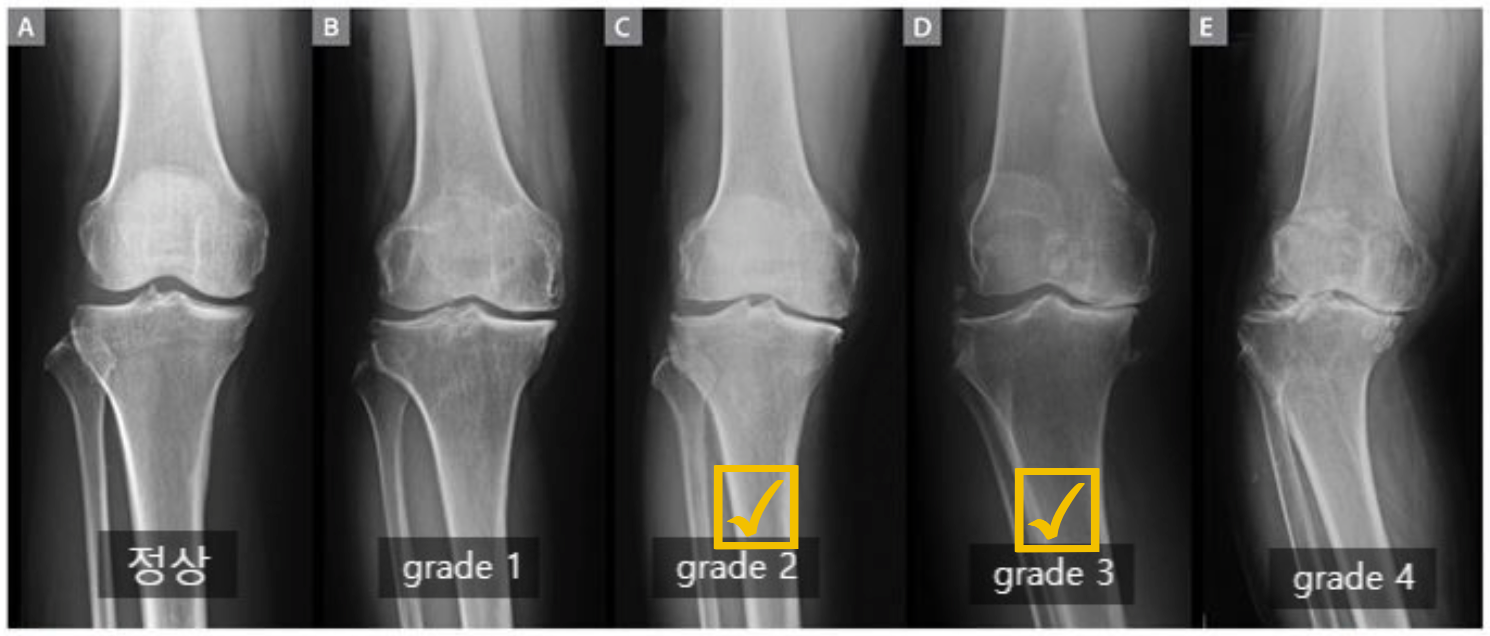

퇴행성 관절염은 진행단계에 따라 초기 - 중기 - 말기로 나눌 수 있으며 X-ray를 촬영하여 1기에서 4기까지 단계로

표현하기도 합니다.

| 단 계 | 단계별 설명 |

| 정상 | 방사선 사진(X-ray)상 별다른 이상이 없을 때 |

| 1 단계 | 경미한 관절공간의 협착이 관찰되고 골극이 형성되는 단계 |

| 2 단계 | 진행된 관절공간의 협착과 확실한 골극이 보이는 단계 |

| 3 단계 | 중증도의 관절공간의 협착 및 골극이 보이는 단계 연골하골의 경화 및 뼈의 변형이 발생 |

| 4 단계 | 관절공간의 현저한 협착 및 골극이 보이며 연골하골의 심한 경화와 뼈와 다리의 변형이 확인되는 단계 |

자가지방유래 기질혈관분획 무릎 관절강 내 주사는 Kellgren-Lawrence grade 2, 3 등급 무릎 골관절염 환자에게 적용가능 합니다.